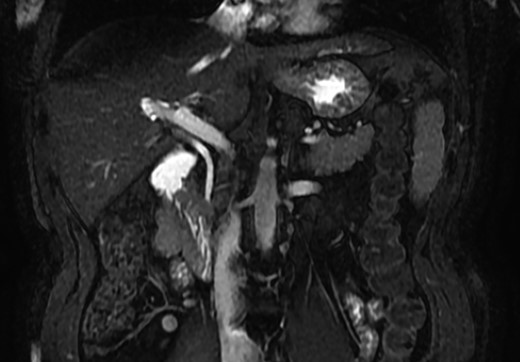

A magnetic resonance cholangiopancreatography (MRCP) confirmed the absence of gallbladder and of the cystic duct and artery (Figs 4–6). No other abdominal anomaly was identified.

MRCP coronal image showing the intrahepatic biliary tract, with good vision of common bile duct, right and left hepatic ducts and anterior branch duct.